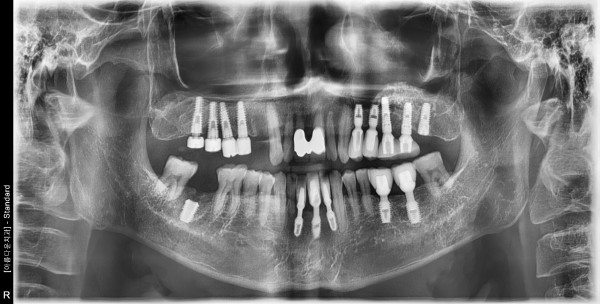

54세 남자환자 / 하악전치&우측구치 발치후 뼈이식 및 임플란트식립